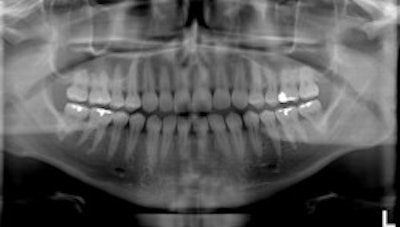

Top, standard panoramic image from a PC-1000 system using a CdTe sensor from Ajat and the PanoACT-1000 tomosynthesis software. Middle, although the anterior teeth are distorted, the posterior teeth no longer have overlapped interproximals. By manually positioning the patient in the system, the contacts are now open. Bottom, the tomosynthesis software then autocorrected the image to bring the front teeth into focus. All images courtesy of Dr. Robert Langlais. |